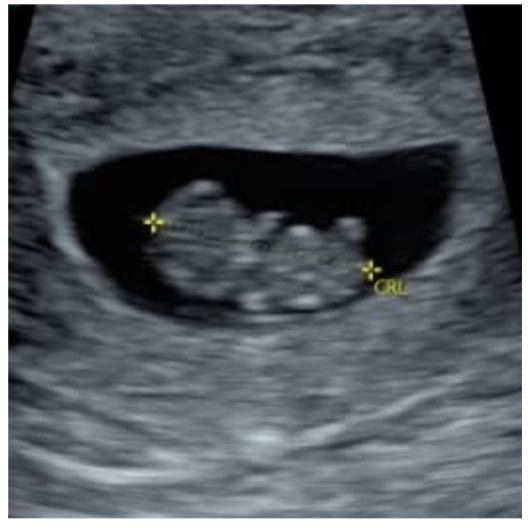

Online Limited Obstetrical Refresher Course to enhance the skills of nurses and sonographers within the pregnancy help community currently performing limited obstetric ultrasound. Available in a convenient and easily accessible on-demand format, the didactic portions of the training can be completed on your own schedule over a six-month period.